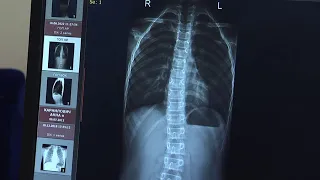

02:23Что такое гипермобильность суставов и когда это небезопасно? Поговорили с детским ортопедомCTVBY28.03.2023